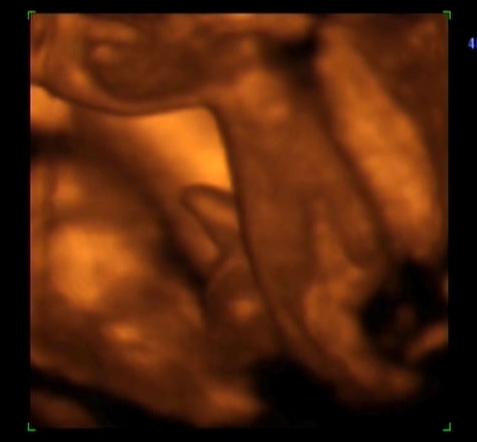

Nagyon szupik a képek és ugy látom "férfiasságban" jól el van eresztve a kis Benedek. :lol:

Gyabi: aranyos a kép a kis Beniről. Nekünk is adtak ilyet amin már látszik a férfiassága :wink: :) Amúgy nagyon kis formás baba. Én nem szavaztam a névről, de nekem is a Benedek tetszett jobban.